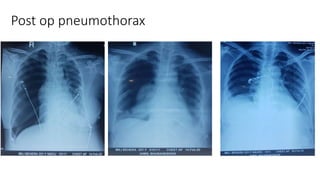

Post op pneumothorax

COMPLICATIONS Pneumothorax Treatment ○ Emergent :14 – 16 Gauge i/v needle in 2nd – 3rd IC space (midclavicular line) ○ Definitive : Tube Thoracostomy To be kept in place till < 100 ml fluid drains /day No air leak Lung fully expanded